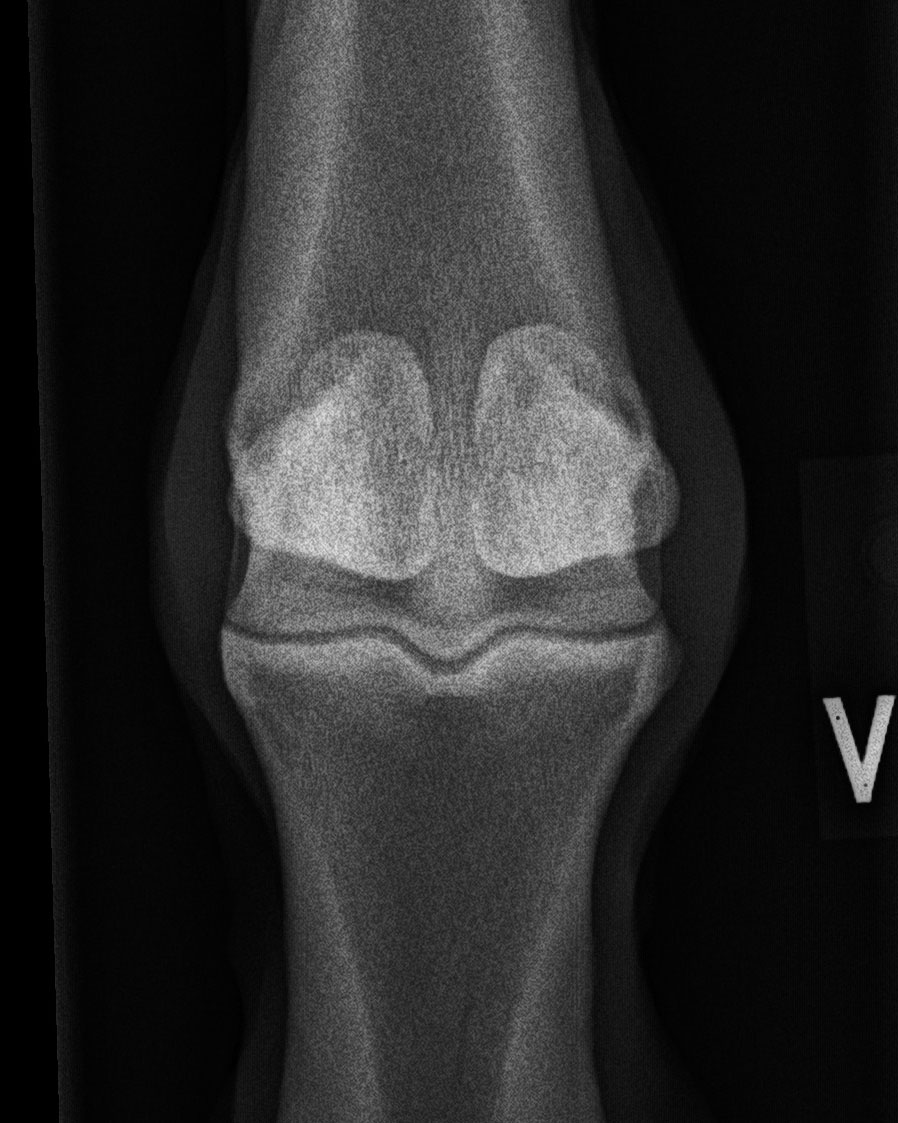

Fesselgelenk - 0°-Aufnahme